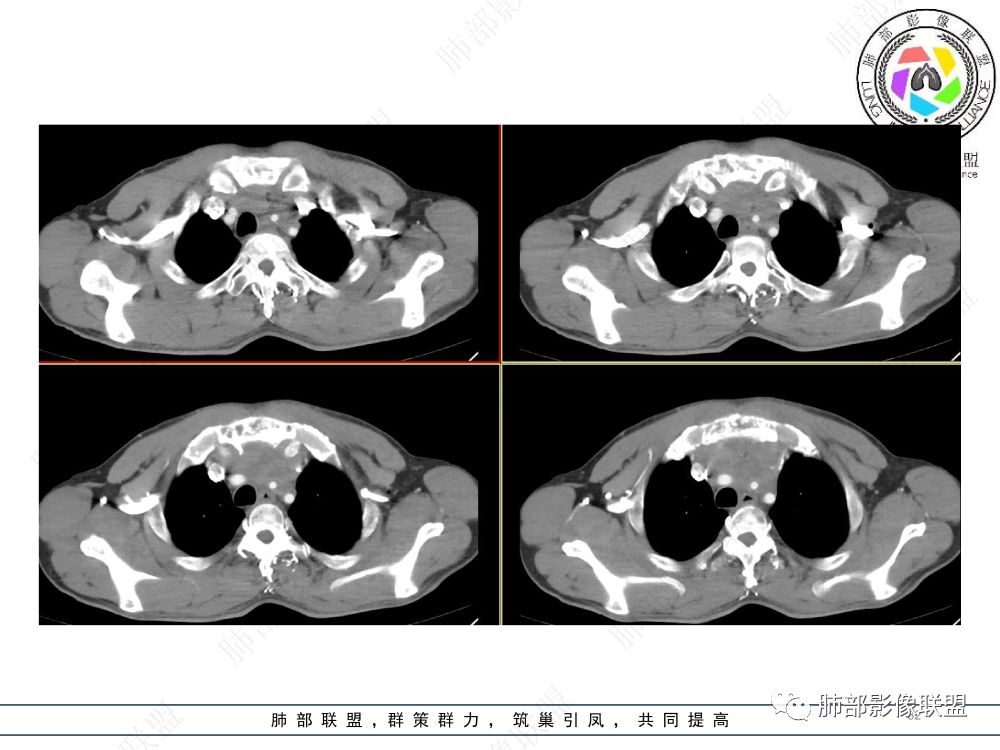

2.影像表现:前上纵隔较大肿块,密度不均,形态不规则,边界不清,有结节样突起,脂肪间隙显示不清。病灶侵犯左无名静脉及上腔静脉,其中左无名静脉闭塞(胸背部侧支循环明显,亦表明回流受阻)。增强后轻中度不均强化。坏死边界欠清晰。可见心包积液,提示心包受侵犯。右侧上叶及纵隔胸膜下结节影,疑胸膜肺转移可能。胸骨柄后缘皮质不完整,疑骨质破坏(未提供骨窗及矢状位图像)。左锁骨上可见肿大淋巴结。